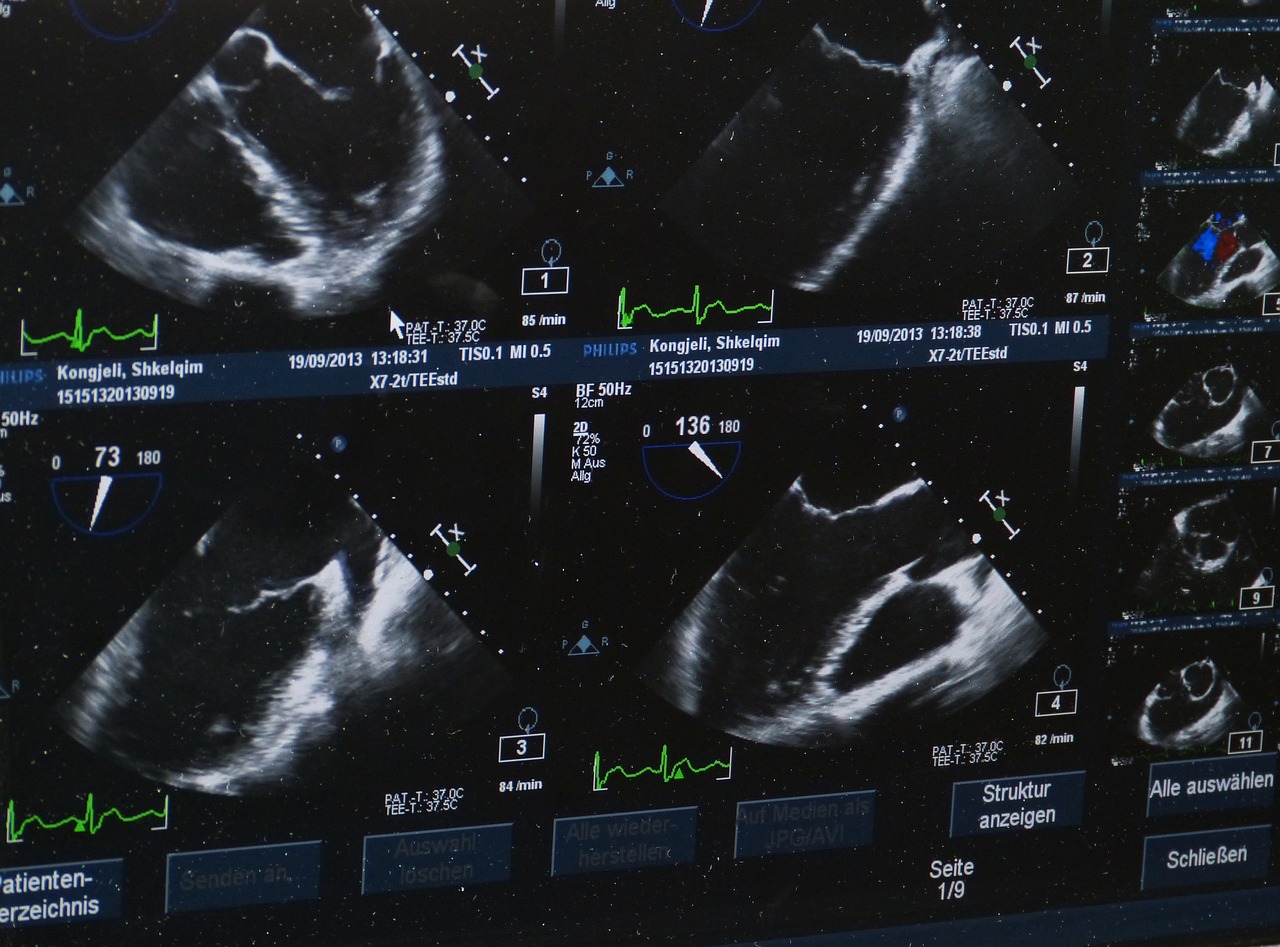

건강검진을 통해 심장, 신장, 간 등 주요 장기의 상태를 확인할 수 있으며, 혈액 검사, 초음파 검사, 엑스레이 등을 통해 숨겨진 질환도 조기 발견할 수 있습니다.

초음파 검사는 내장 기관의 상태를 상세히 확인하는 데 사용되며, 엑스레이는 뼈나 폐의 상태를 확인하는 데 유용합니다.

심장에 이상이 있을 경우 심전도나 심장 초음파 검사를 시행할 수 있습니다.

심장 검사는 노령견에게 특히 중요하며, 보통 15만 원에서 25만 원 정도의 비용이 발생합니다.